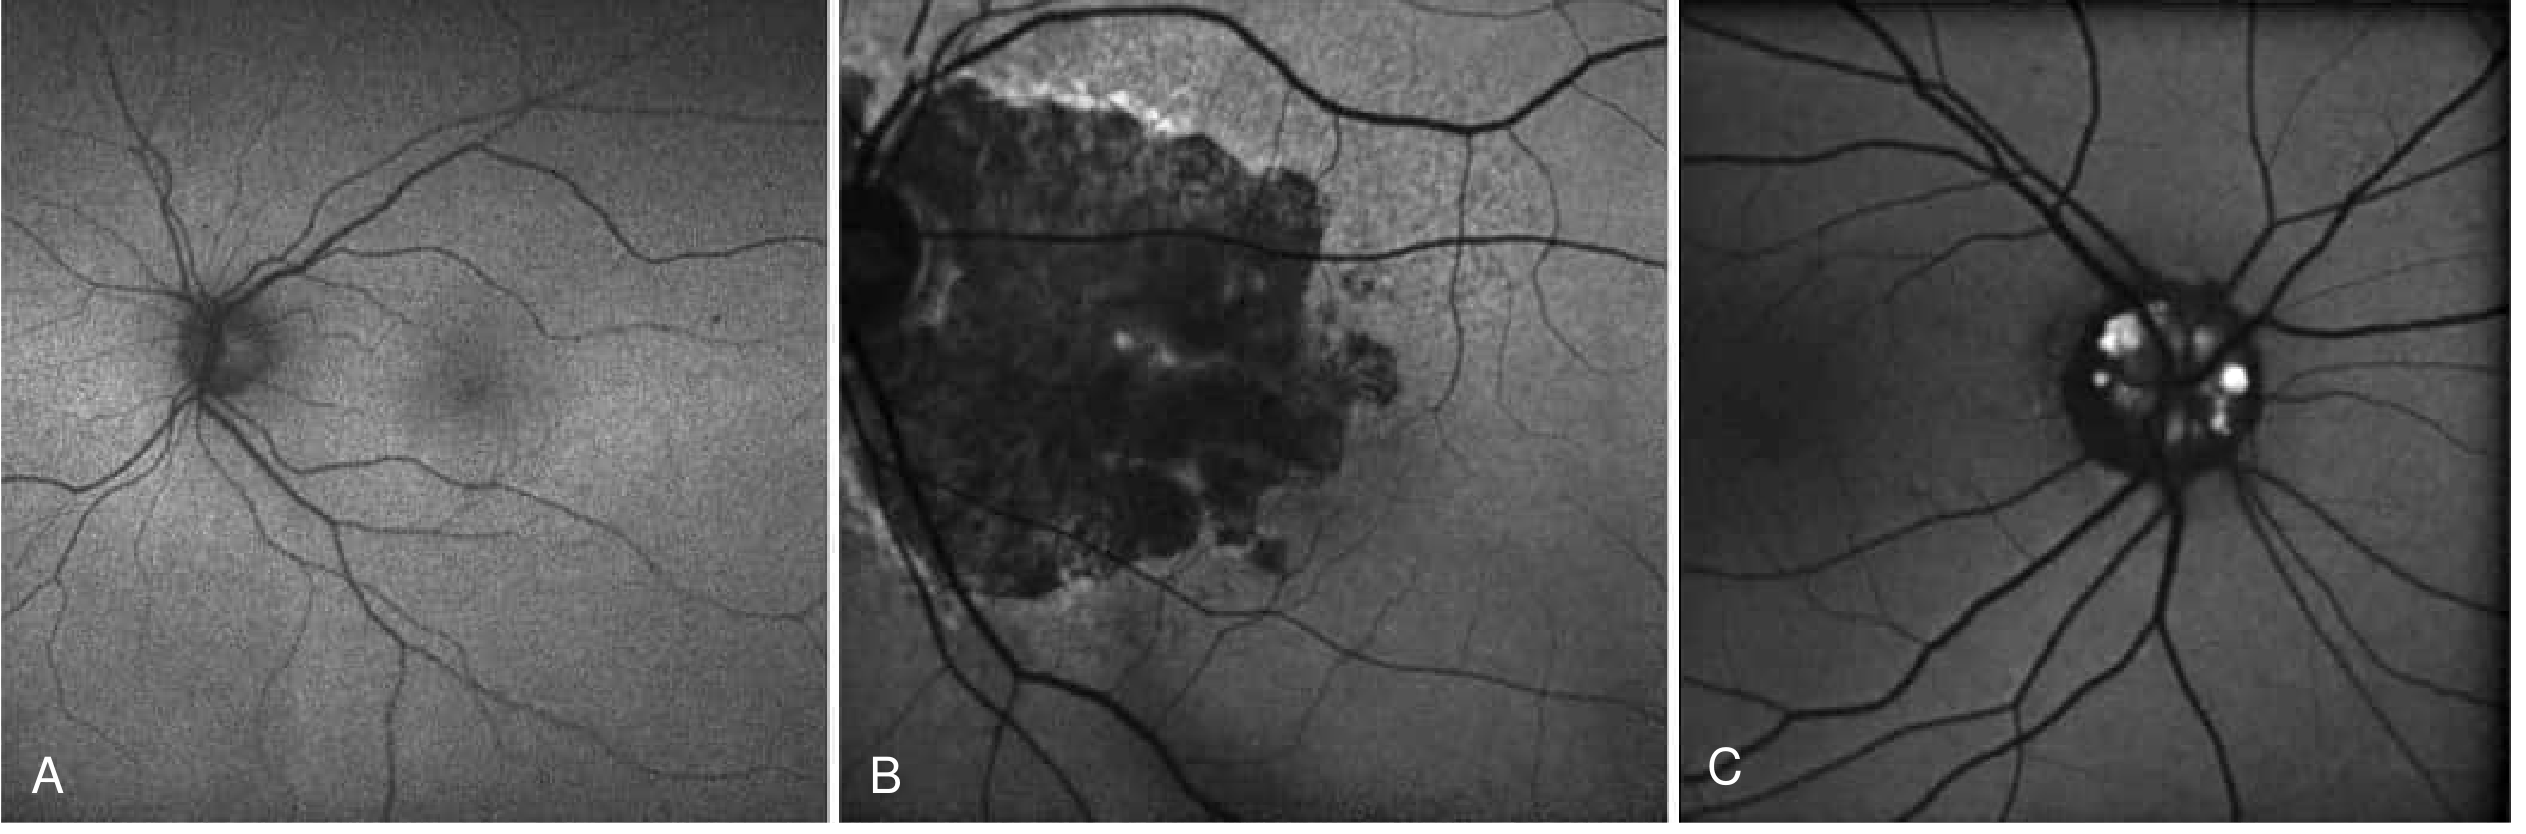

FAF Images – Normal, Geographic Atrophy, Optic Disc Drusen

A – Normal FAF. B – Geographic atrophy (central hypo-AF). C – Optic disc drusen (hyper-AF foci on optic nerve). (Bradley & Daroff's Neurology)

FAF: A – Normal, B – Geographic atrophy (hypo-AF), C – Optic disc drusen (hyper-AF)

Fig: A – Normal FAF with low background signal. B – Geographic atrophy in AMD appearing as well-demarcated hypo-AF zone. C – Optic disc drusen appearing as hyper-AF foci. (Bradley & Daroff's Neurology)